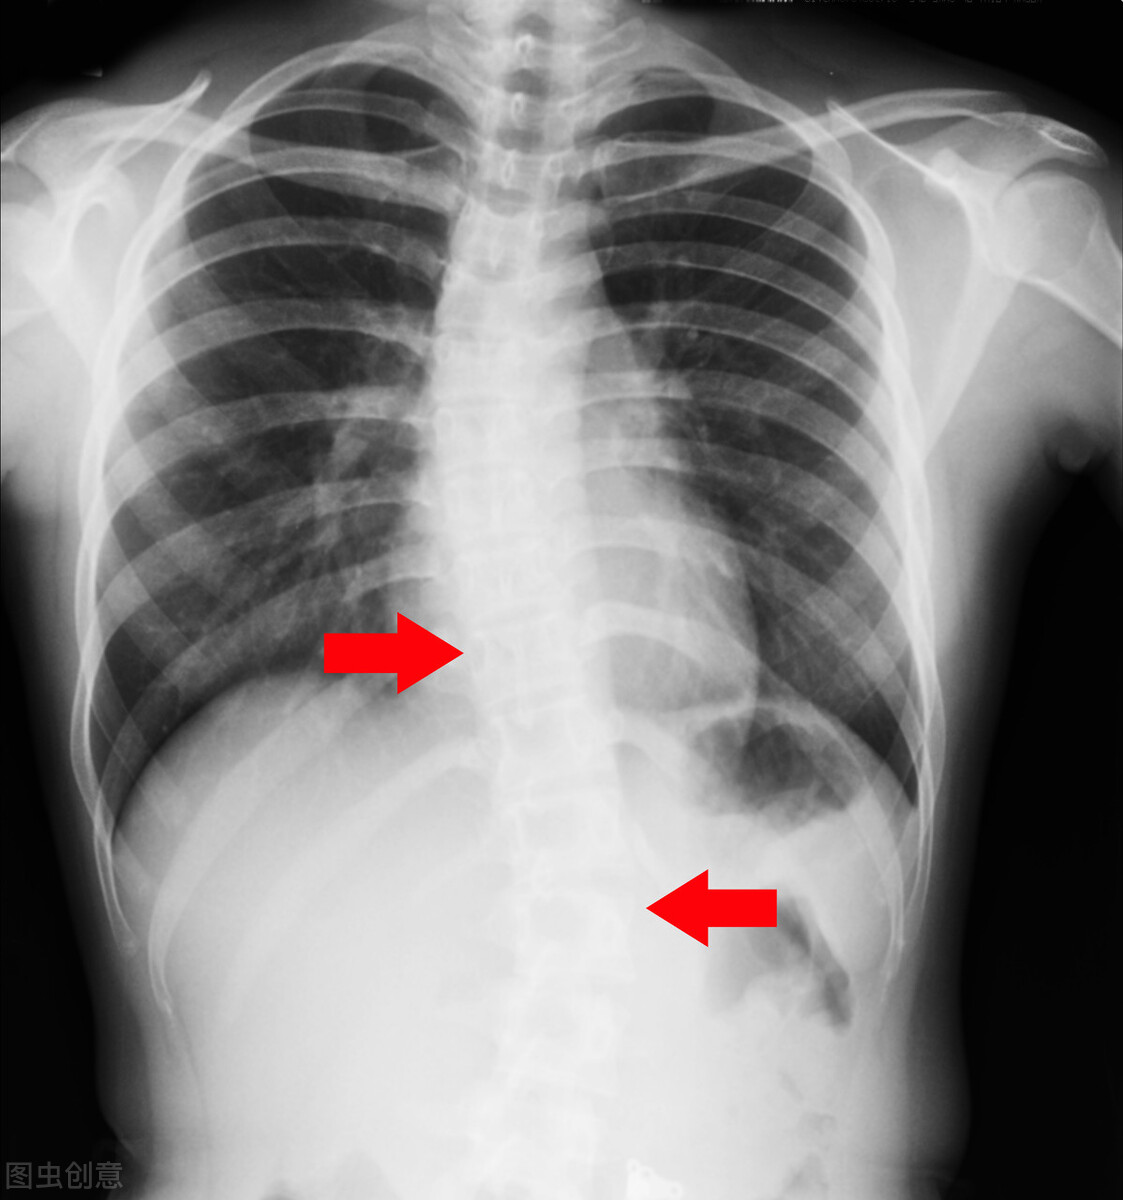

如果从正面看脊柱在侧向上发生了弯曲,就叫做脊柱侧弯,在X光片上,如果它的侧向弯曲度大于10度,在医学上就可以确诊,换句话说,它就具有治疗的意义和价值。如果侧弯过大,通常角度大于40度,就要考虑手术治疗,根据统计,大概有2%~3%的人会出现脊柱侧弯,但是不是所有的脊柱侧弯都需要治疗。